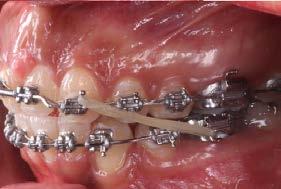

La paciente fue tratada con aparatología fija MBT slot 0.022”, se utilizaron bandas en primeros molares superiores e inferiores y tubos en segundos molares superiores, se realizaron extracciones de los dientes 11, 21, 34 y 44. Se colocaron los brackets de centrales en laterales, los de laterales en caninos y los de caninos en premolares.

En la fase de alineación se utilizó una secuencia de arcos comenzando con el arco 0.012” NiTi, 0.014” NiTi y 0.016” Niti. Se realizó la tracción del diente 21 y se mantuvo en boca hasta comenzar la fase de trabajo, posteriormente se realizó la extracción (Figura 3).

Durante la fase de trabajo se realizaron sets de intrusión y utilización de close coil; una vez cerrado el espacio entre los incisivos laterales, se indicó el uso de elásticos de clase III 3/16 4.5 oz para corregir la mordida borde a borde (Figura 4).

Se remitió a la especialidad en prostodoncia para valoración, indican abrir espacios en anteriores para su posterior restauración. Se retiró aparatología fija y se entregó retención con circunferenciales y fijo inferior (Figura 5).